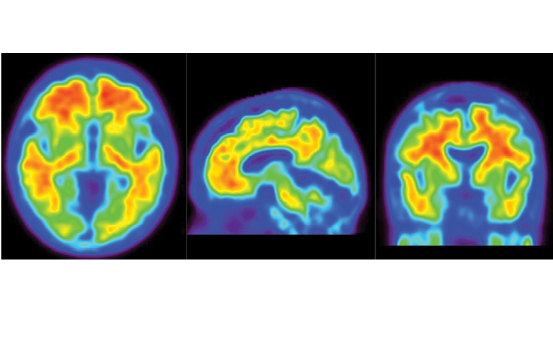

The announcement comes as a landmark international research paper has just been published, HERE, looking into the efficacy and safety of donanemab as demonstrated in a Phase III trial with 1,736 participants, with early symptomatic Alzheimer's disease and amyloid and tau pathology.

Participants showed 35% slowing of clinical (cognitive and functional) decline over 18 months, while across the whole study group there was a 22% slowdown in disease progression.